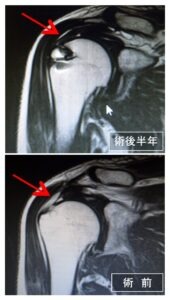

術後に再建腱板の評価をMRIで行います

菅谷分類

| Type1 | 腱板に厚み,一様に低信号 |

|---|---|

| Type2 | 腱板に厚み,一部に高信号混在 |

| Type3 | 連続性は保たれているが厚みがない |

| Type4 | 一部のスライスで連続性がない |

| Type5 | 連続性の途絶部分が大きい |

Type1(最もいい)~5(最も悪い)

4、5(再断裂)であっても求心位がとれていれば問題ありません。